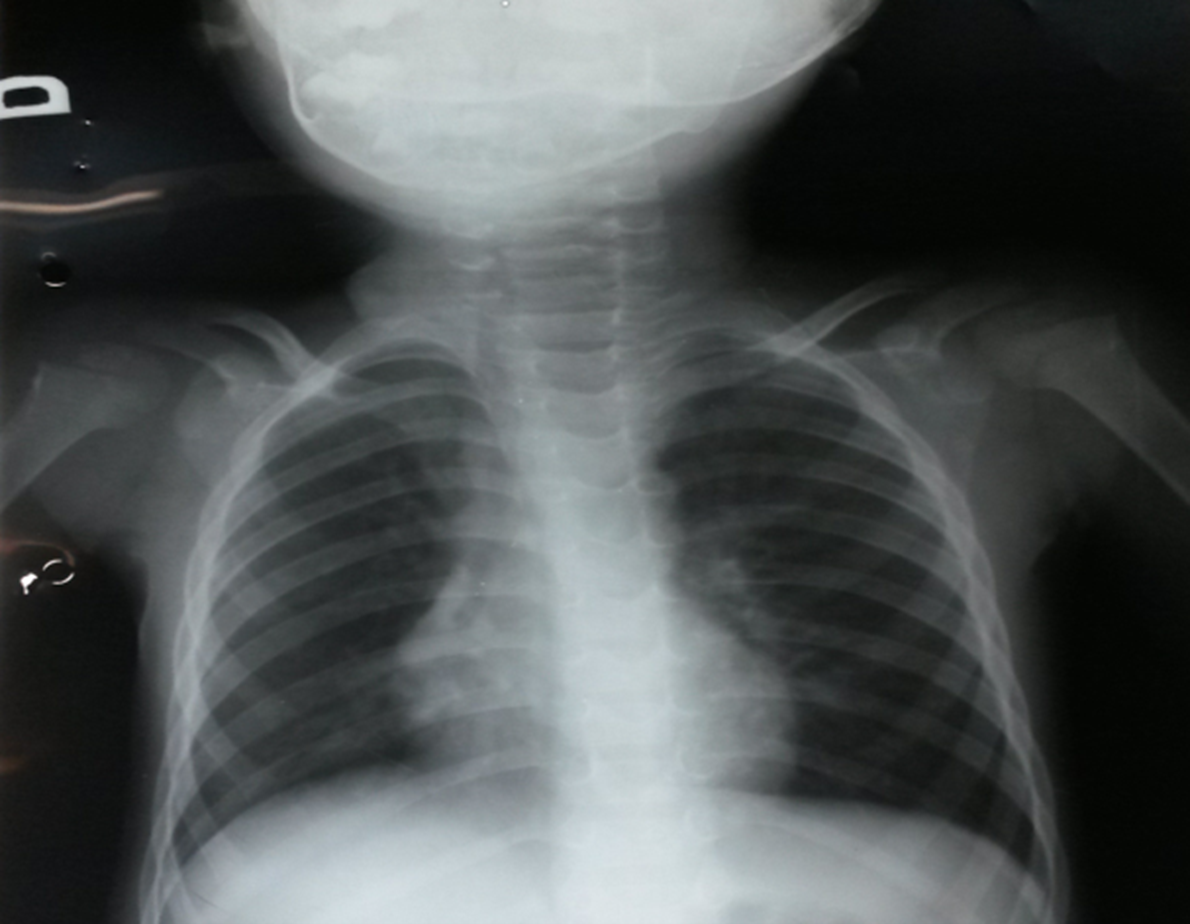

Briefly highlighting some unseen evidence of two comorbid COVID-19 patients

Abdullah, Muhammad Salman, Sher Ali, Riaz Muhammad, Aiman Waheed, Muddasir Khan, Sana Ullah, Carlos Augusto Fernandes de Oliveira